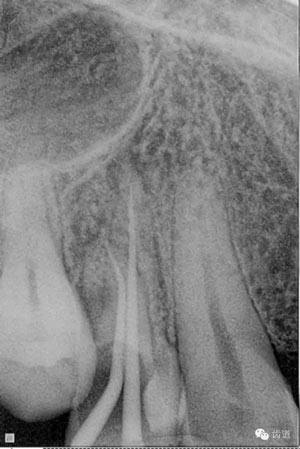

處理:去除暫封物,超聲根管蕩洗,清除氫氧化鈣糊劑,干燥根管,拍片顯示2506牙膠尖適合,根管內(nèi)放置AH plus,熱牙膠連續(xù)波根管充填。

數(shù)碼x攝影顯示:近中頰根及腭根根管充填恰填,遠(yuǎn)中根管有遺漏。

顯微鏡下反復(fù)探查根管,未探及遺漏根管口,放置棉球,zoe暫封。轉(zhuǎn)診上級(jí)醫(yī)生處理。